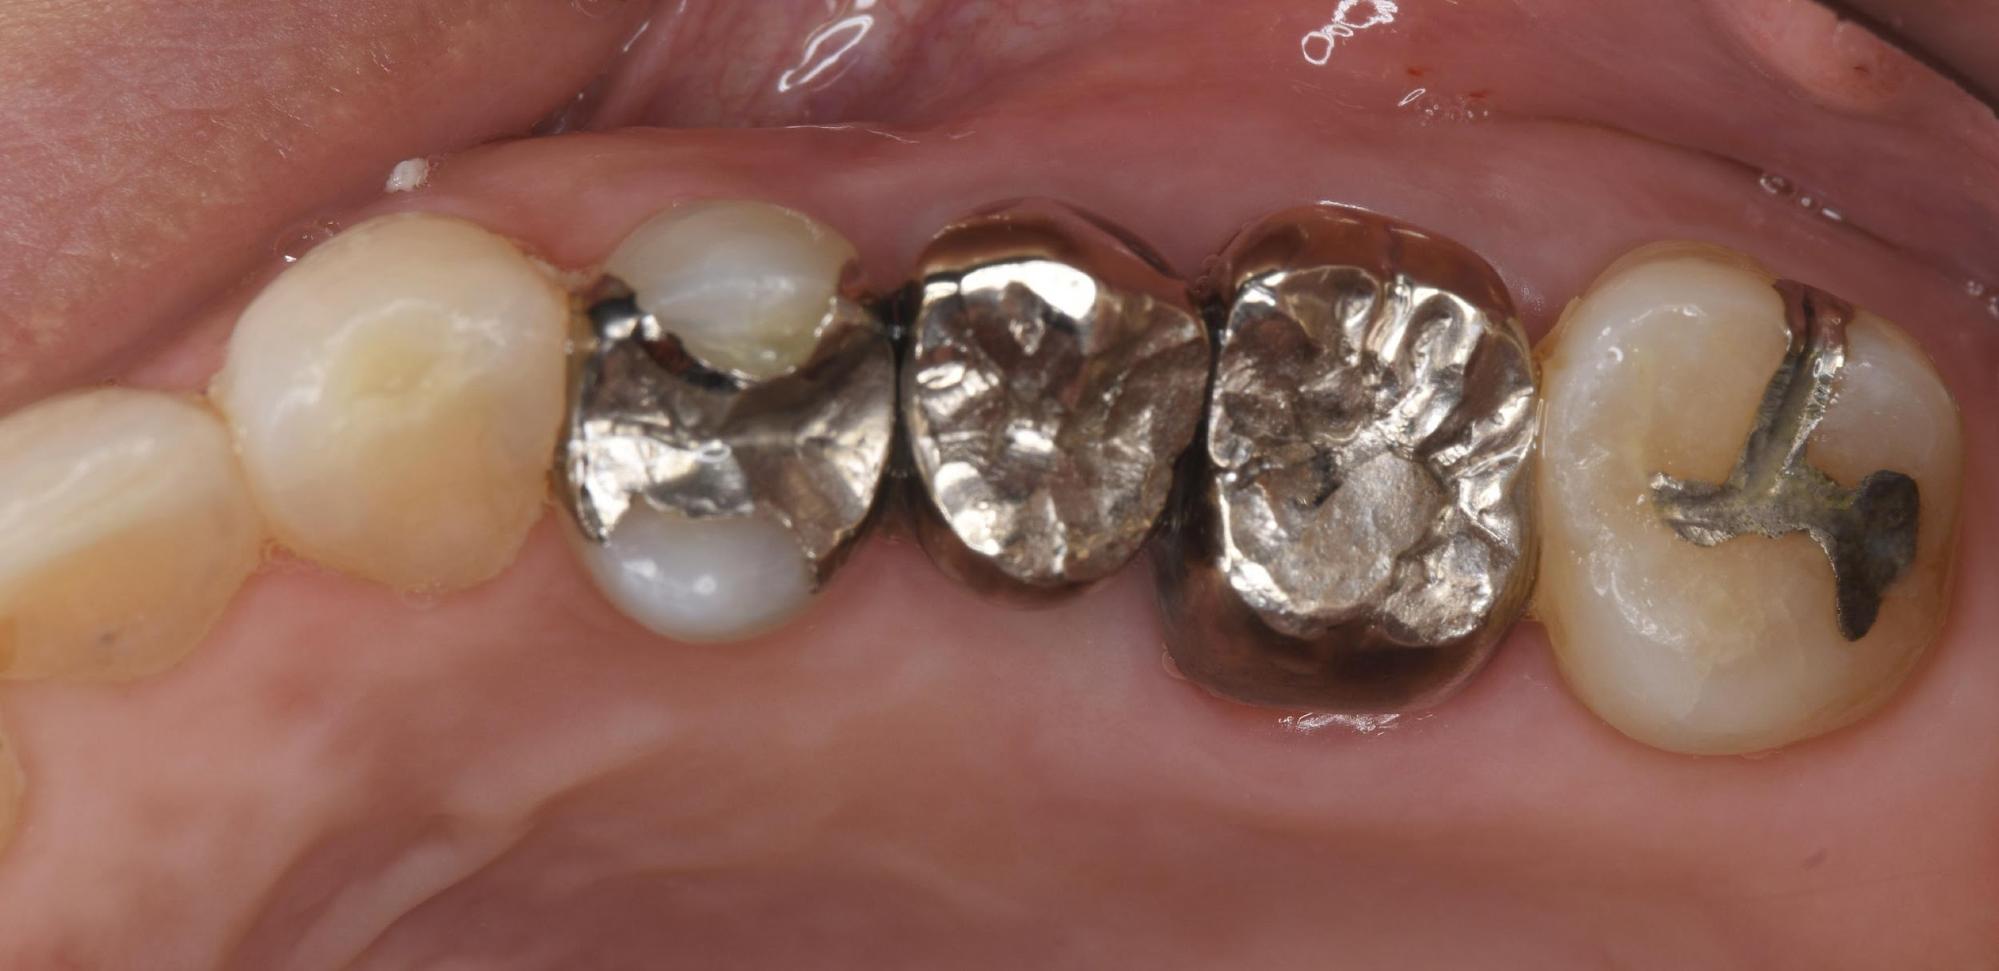

まずはレントゲン撮影に加え、3次元的な骨の状態や歯根の向きを正確に把握できる「歯科用CT」による診査を行いました。

画像診断の結果、左上の銀歯の下でむし歯(二次カリエス)が重度に進行していることが判明しました。表面の銀歯を一見しただけでは分かりにくいのですが、内部でむし歯菌が感染を広げており、歯の根の方までボロボロの状態になっていました。

一度治療をして詰め物や被せ物(銀歯など)をした歯が、その内側で再びむし歯になってしまうことを「二次カリエス」と呼びます。

銀歯などの保険適用の金属は、経年劣化により接着剤が溶け出したり、金属自体が変形したりすることで、歯との間に目に見えない隙間が生じやすくなります。そこからむし歯菌が侵入し、気づかないうちに内部でむし歯が進行してしまうのです。神経を抜いている歯の場合、痛みを感じにくいため、発見が遅れ、今回のように抜歯を余儀なくされるケースも少なくありません。

診査の結果、残念ながらこの歯を保存(残すこと)は不可能であり、「抜歯」が必要であるという診断に至りました。